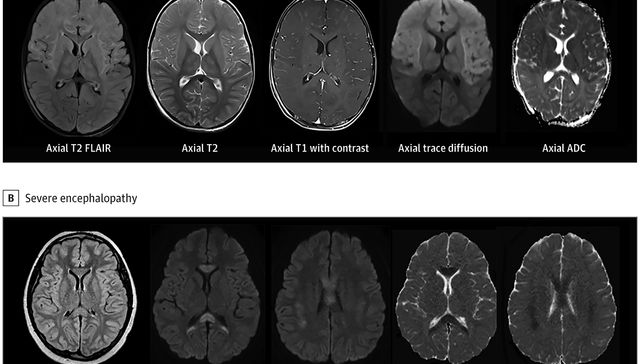

Algunos niños con un síndrome relacionado con la COVID desarrollan síntomas neurológicos